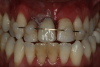

Fig 6. Image of the patient’s mature smile.

Figure 6

Figure 6 and Figure 7 depict a mature smile with many implant restorations. An analog impression was sent to the laboratory. The impression was scanned by the laboratory, a model was created virtually, and the implant dimensions and position were defined. The 3D surgical guide was fabricated (Figure 8), allowing the patient to receive his therapy swiftly and predictably. Tooth No. 8 was extracted, and the implant was placed and immediately loaded with an acrylic provisional treatment crown (Figure 9). The screw-retained treatment crown was fabricated in-office from a previously completed diagnostic wax-up.